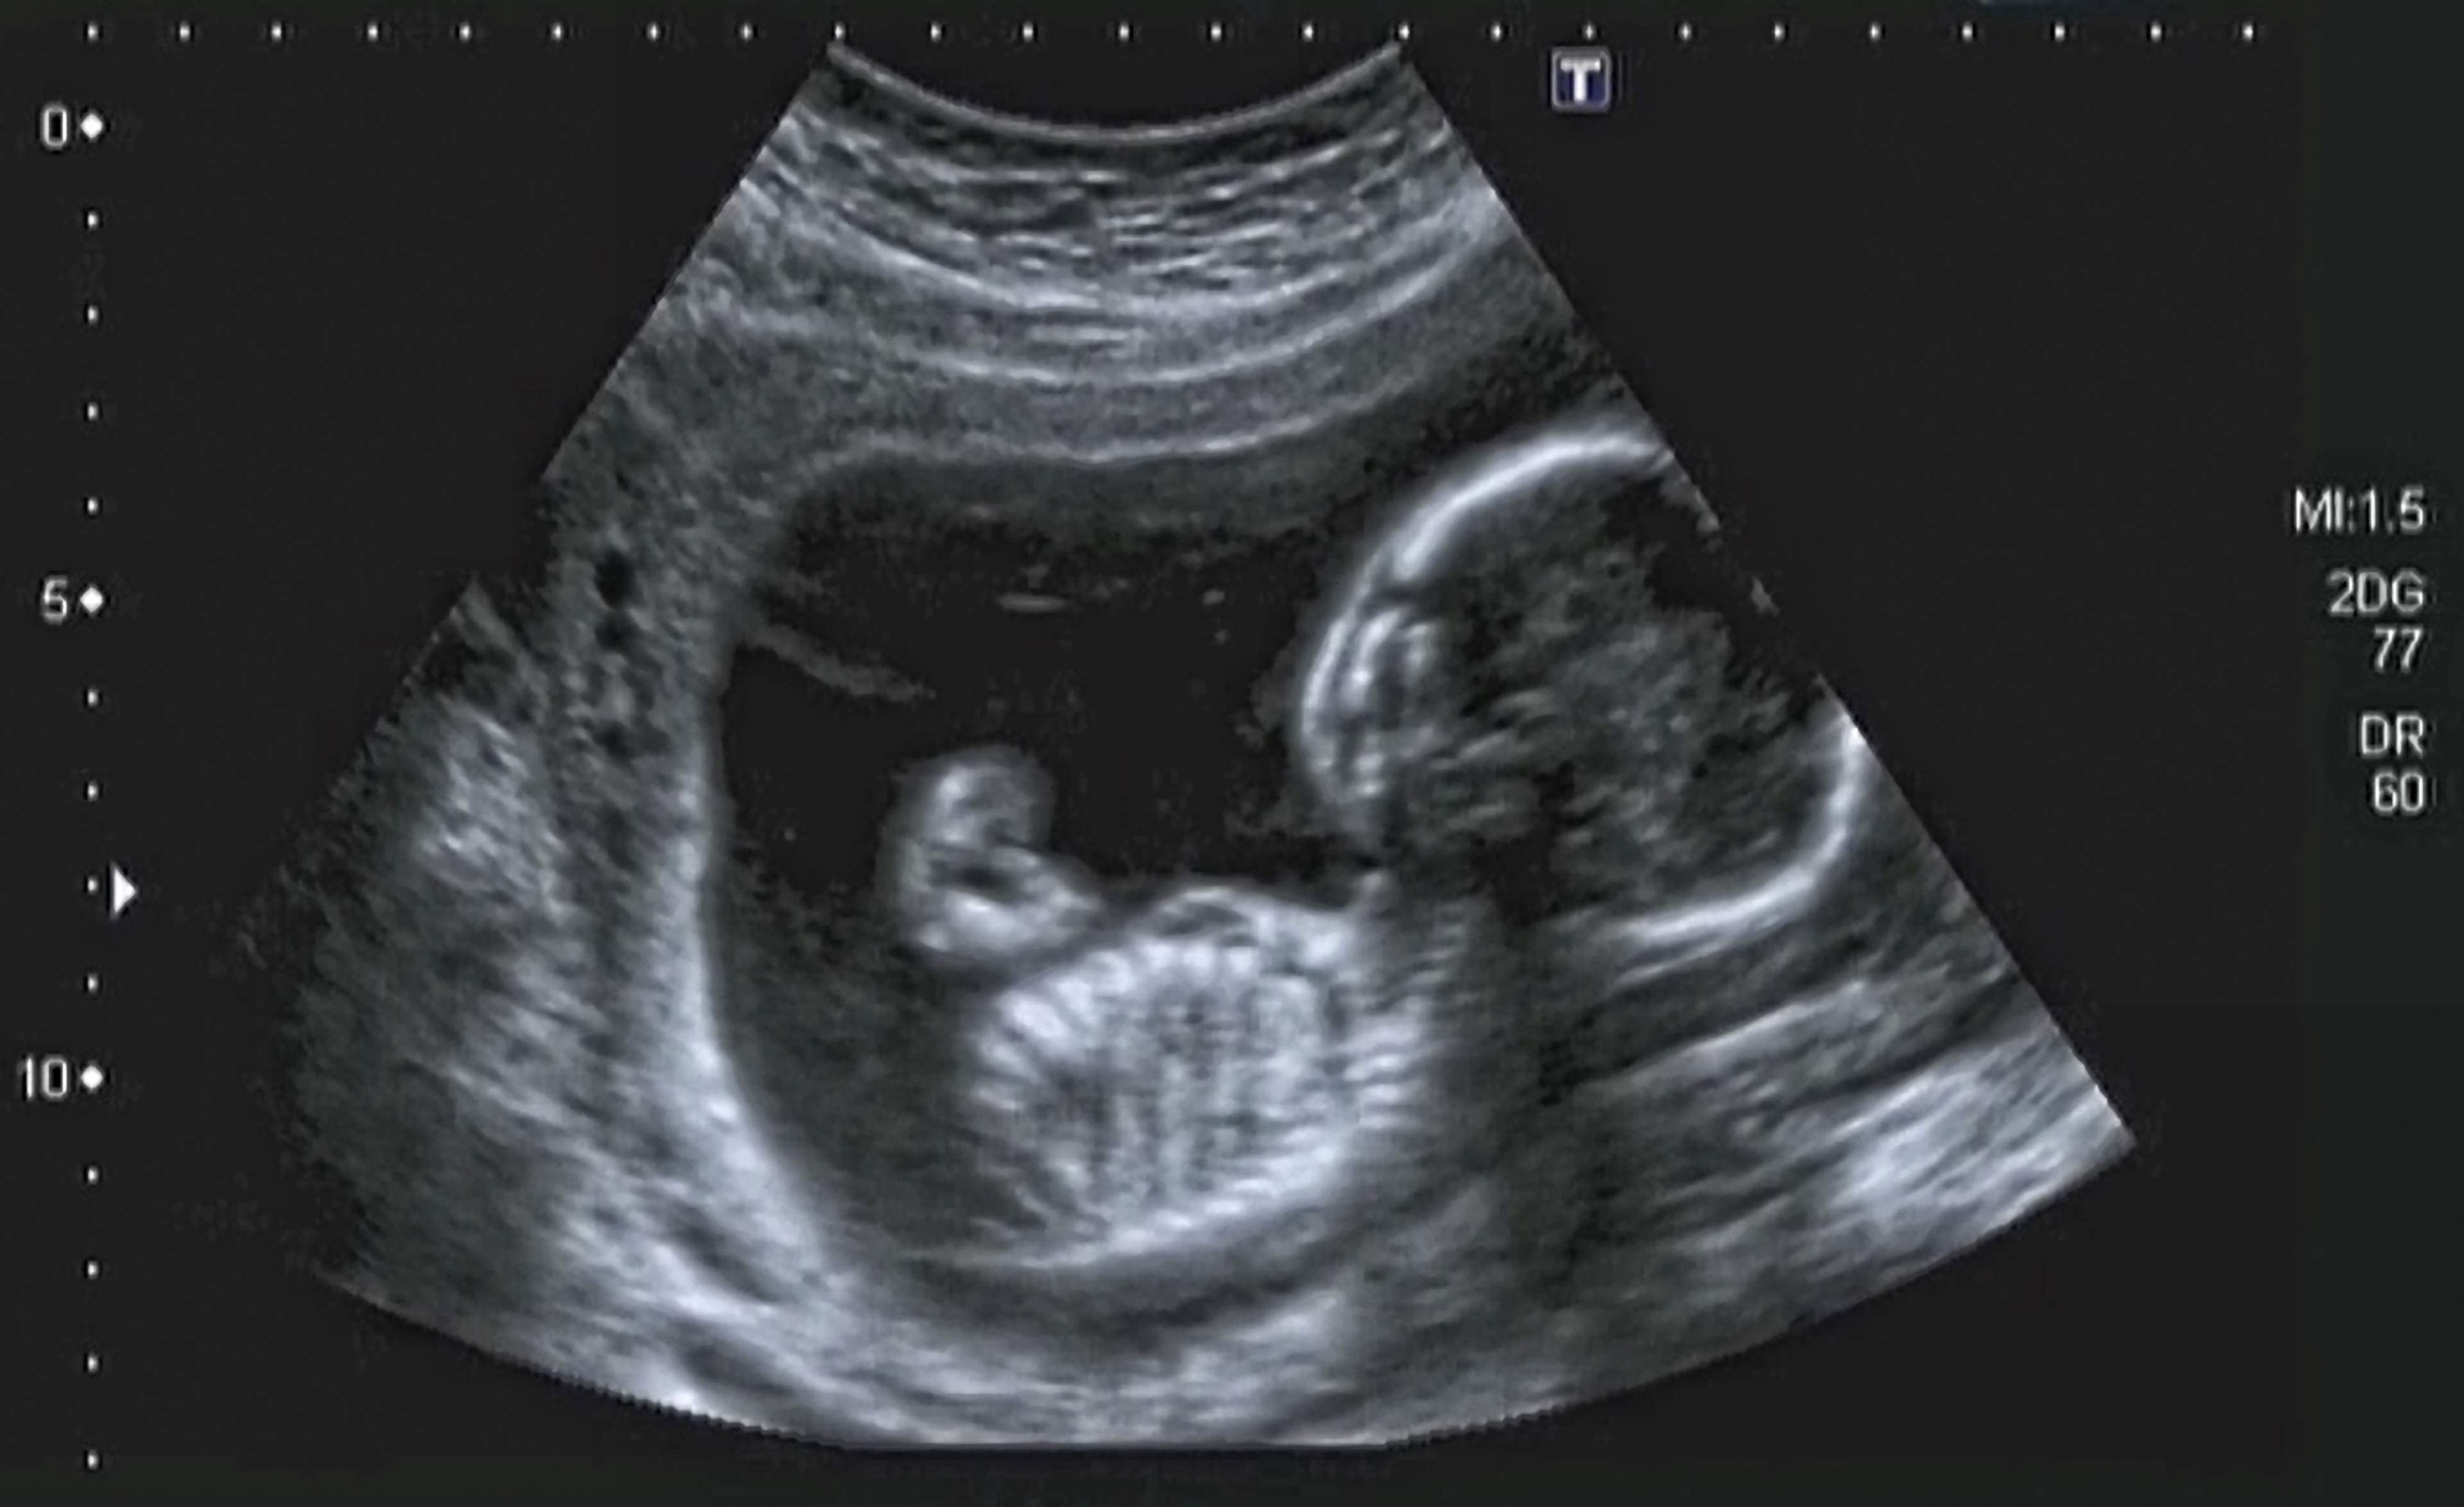

Isälle tai puolisolle vauvan olemassaolo konkretisoituu keskiraskauden aikana. Tällöin vauvan sydämenlyönnit ovat jo kuultavissa ja potkut tunnettavissa äidin vatsanpeitteiden läpi. Ultraäänikuvassa vauvan piirteet näkyvät selvästi. Loppuraskaudessa, kun vatsa kasvaa, hyvän asennon löytäminen ja oman kehon rajojen hahmottaminen voivat olla naiselle haasteellisia arjen toiminnoissa. Vaikka raskaana oleva nainen muuttuu ulkoisesti, sisimmässään hän on sama ihminen kuin ennenkin. Naisen tulee ymmärtää, että hän voi näyttää aidosti hyvältä myös odotusaikana. Puolison hyväksyntä, ymmärrys ja välittäminen rohkaisevat naista iloitsemaan naisellisuudestaan loppuraskaudessa.

olemalla mukana äitiysneuvolassa. Ensimmäinen ultraäänikuva vauvasta saa lapsen tuntumaan todelliselta. Lisätietoa alkuraskauden tutkimuksista Naistalossa: